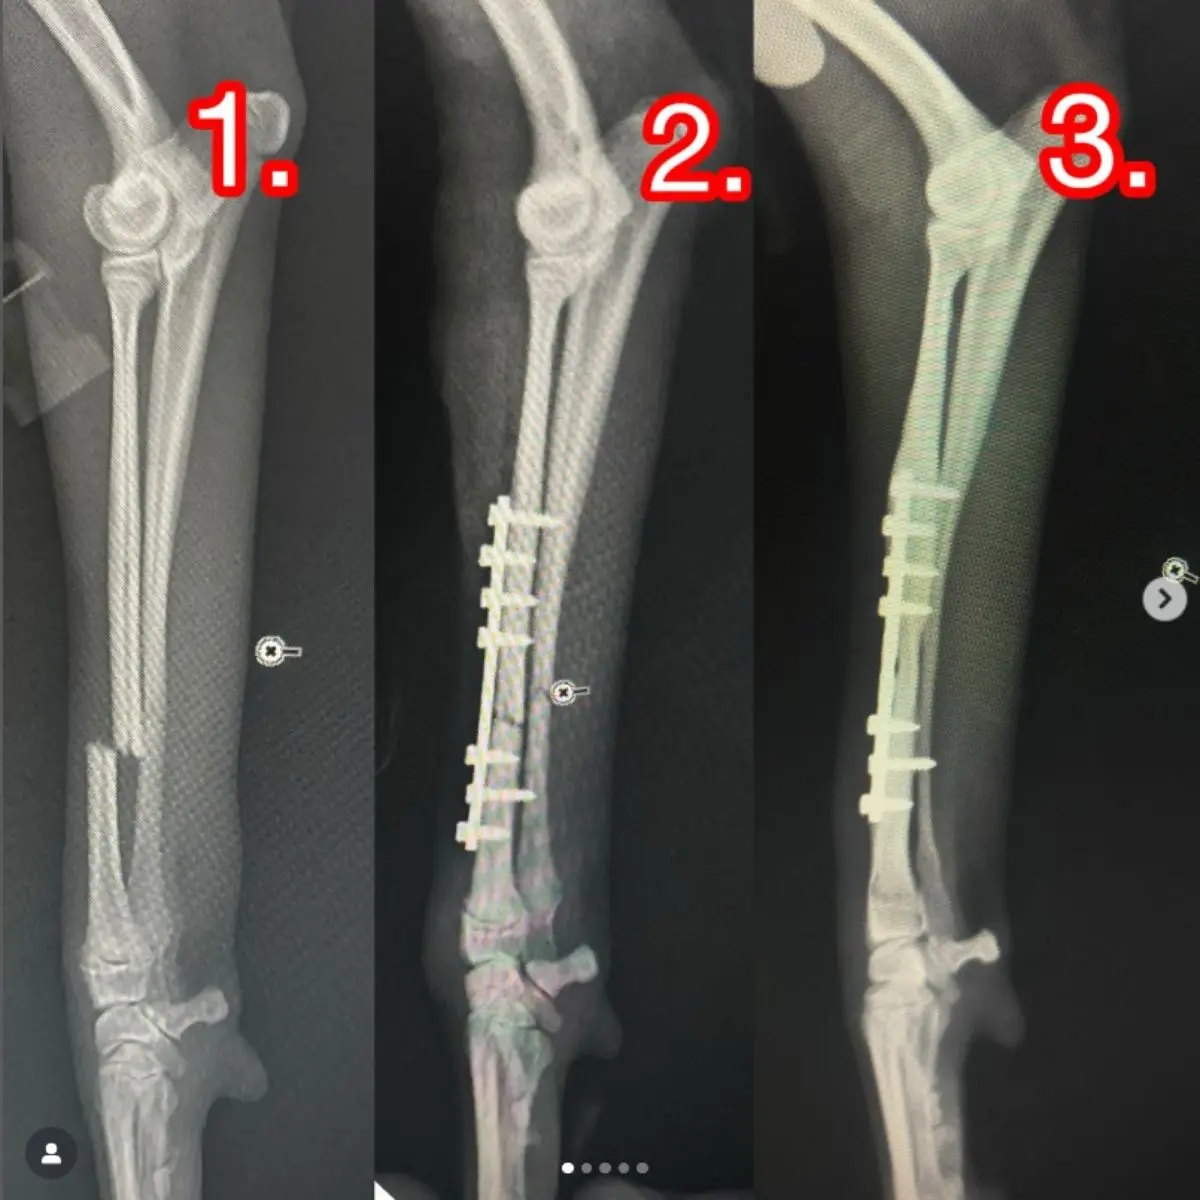

Vida ile Sabitleme ve Düzeltme: Kemik kırıklarını stabilize etmek ve doğru pozisyonda kaynamasını sağlamak için uygulanır.

Pin ile Sabitleme ve Düzeltme: İnce metal çubuklar kullanılarak kırıklar ve eklem deformiteleri düzeltilir.

Eksternal Fiksatör ile Sabitleme ve Düzeltme: Kırık veya çıkıkları dışardan sabitleyen cihazlarla tedavi edilir.

Plak ile Sabitleme ve Düzeltme: Kemiklerin doğru şekilde birleşmesi için cerrahi olarak plak ve vida sistemi uygulanır.